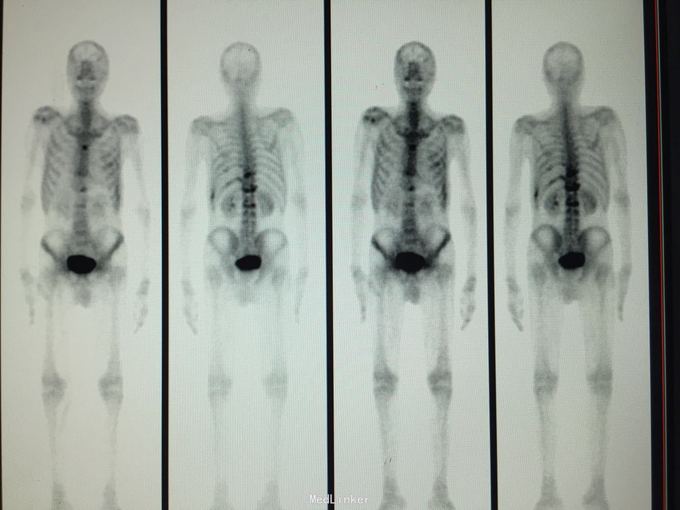

MRI示:肋骨,胸椎多发骨转移 CT示:胃Ca术后:腹膜后淋巴结转移,左侧胸膜多发转移,左侧后壁转移并T10锥体及左侧横突,第10.11后肋转移骨质破坏,骨质疏松并T12及L2压缩骨折 核医学ECT示:多发骨转移

化疗加放疗治疗 核医学建议:行锶89治疗骨转移 大家集思广益,看看这个病人下一步做何治疗